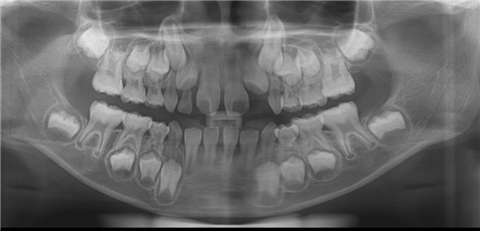

| 턱뼈 속에 영구치들이 젓니 뿌리를 흡수시키며 자라나고 있다 |